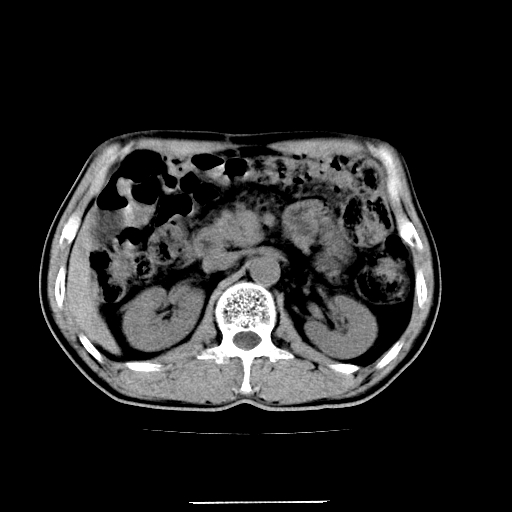

患者男,64岁,胃癌术后三个月,无明显不适。请讨论一下胰头前方小圆形低密度影为淋巴结还是肠管?

肠管吧.另外右肾见盂旁囊肿.

肠管.右肾见盂旁囊肿.

增强第6幅图上有气液平相通,是肠管,右肾低密度灶形态不规则似有壁结节,不除外转移.

应该考虑是肠管,理由1、平扫和增强对比,形态和内部的密度有明显改变。2、增强图片可见明显气液平面。

是肠管影,肠壁有强化。

一个形态变化大应该是肠管。

另一个上下观察不成形,强化也不符合淋巴结表现故考虑术后改变。

是肠管影。还有右侧肾盂旁囊肿。

胰头右侧低密度影卡考虑为肠管;胰头前部低密度影,增强环形强化,结合临床首先考虑转移灶,其次考虑淋巴结结核(中心干酪性坏死)。